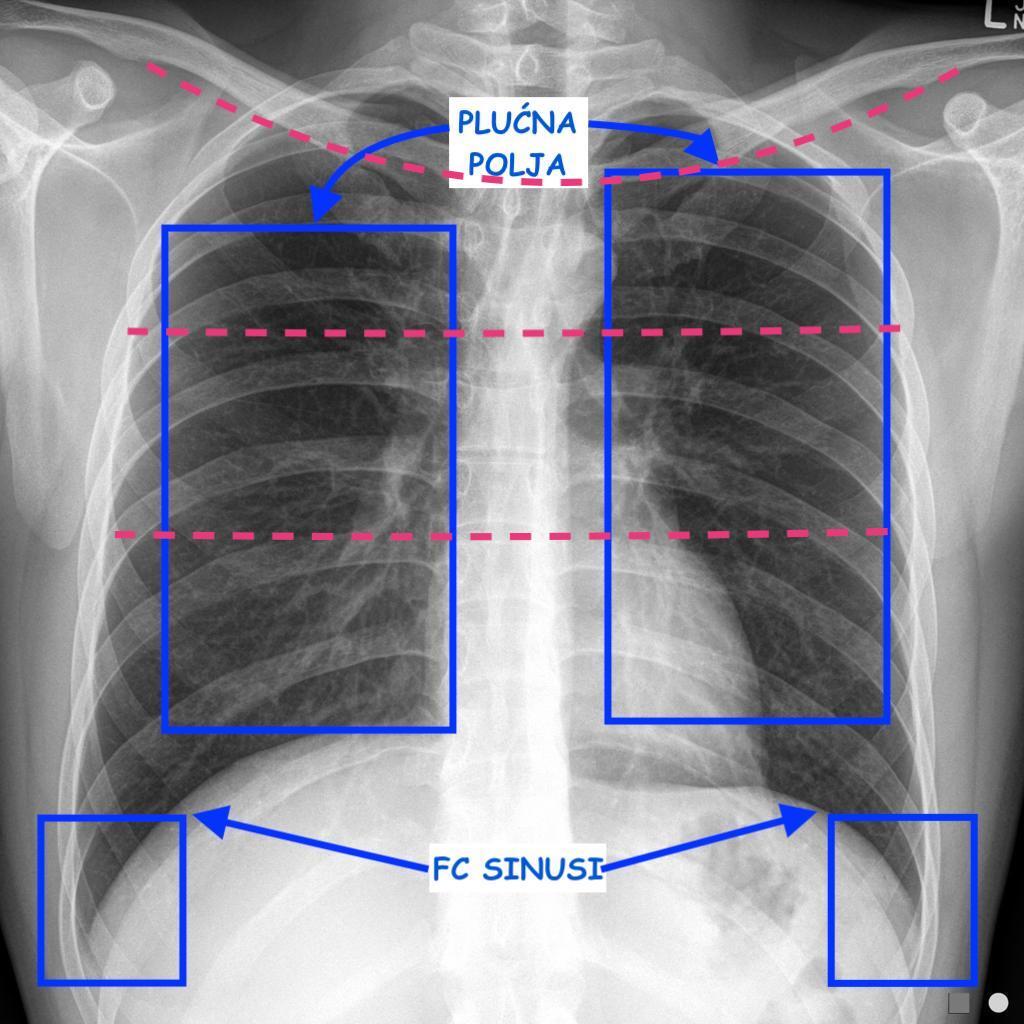

Analiza RTGa započinje uvidom u stanje mekih tkiva i koštanih elemenata grudnog koša, da bi otklonili sumnju na potkožni emfizem ili eventualno neku patologiju rebara. Gledamo simetriju plućnih polja sa desne i sa lijeve strane, poredimo vrhove pluća koji također moraju biti simetrični, položaj traheje i njene bifurkacije (može biti pomjerena udesno zbog aorte koja jaše iznad desnog principalnog bronha), te centralnu medijastinalnu sjenu. Pažnju posebno treba obratiti na hiluse(naročito na limfne čvorove ako su uvećani - sarkoidoza), kakvog su izgleda (transparencije), plućnu vaskularnu šaru koja polazi iz hilusa, zatim kardiofrenični i kostofrenični ugao (fiziološki oštri i transparentni, bez sadržaja. Kardiofrenični ugao može biti zasjenjen u inspiriju v. cavom inferiror i hepatičnim venama). Mjerimo kardio-torakalni omjer koji predstavlja razliku između u utrašnjeg dijametra toraksa i vanjskog dijametra srca. Normalan KT omjer iznosi 1/3 tj. srce zauzima 1/3 ukupnog dijametra toraksa. KT omjer veći od 0.75 je mogući znak kardiomegalije. Potrebno je analizirati desnu i lijevu konturu centralne medijastinalne sjene i opisati eventualne promjene.

Kada kažemo simetrično, mislimo na sve ono što je fiziološki, a sve što nije simetrično može predstavljati varijaciju ili patološko stanje. Sve promjene treba opisati detaljno, tj. potrebno je navesti lokaciju, vrstu promjene i njenu veličinu. Više o tome možete pročitati u članku “Patološke primjene na RTG P/C”.